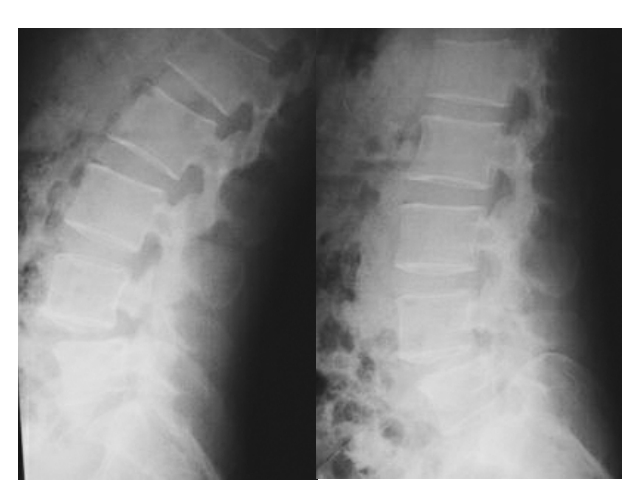

腰椎动力位片即腰椎屈伸位动态X线片检查,腰椎动力位片是诊断腰椎不稳的主要依据和手段(图22)。腰椎间盘突出症有很多情况会出现腰椎不稳,而腰椎不稳是不能仅仅通过腰椎正、侧位片来判断的,需要通过腰椎正、侧位片来诊断,因为腰椎是通过骨性连接,软组织来稳定的,所以在不同的体位或者负重状态时会出现不同的X线片变现,所以通过腰椎动力片可以很好的显示腰椎的稳定情况。如图所示,在腰椎腰4椎体向前移位加大,提示此椎体过伸、过屈位上显示明显不稳。

图22 腰椎动力位片(腰椎过伸、过屈位)